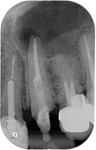

Post removal cases

Premolar retreatment